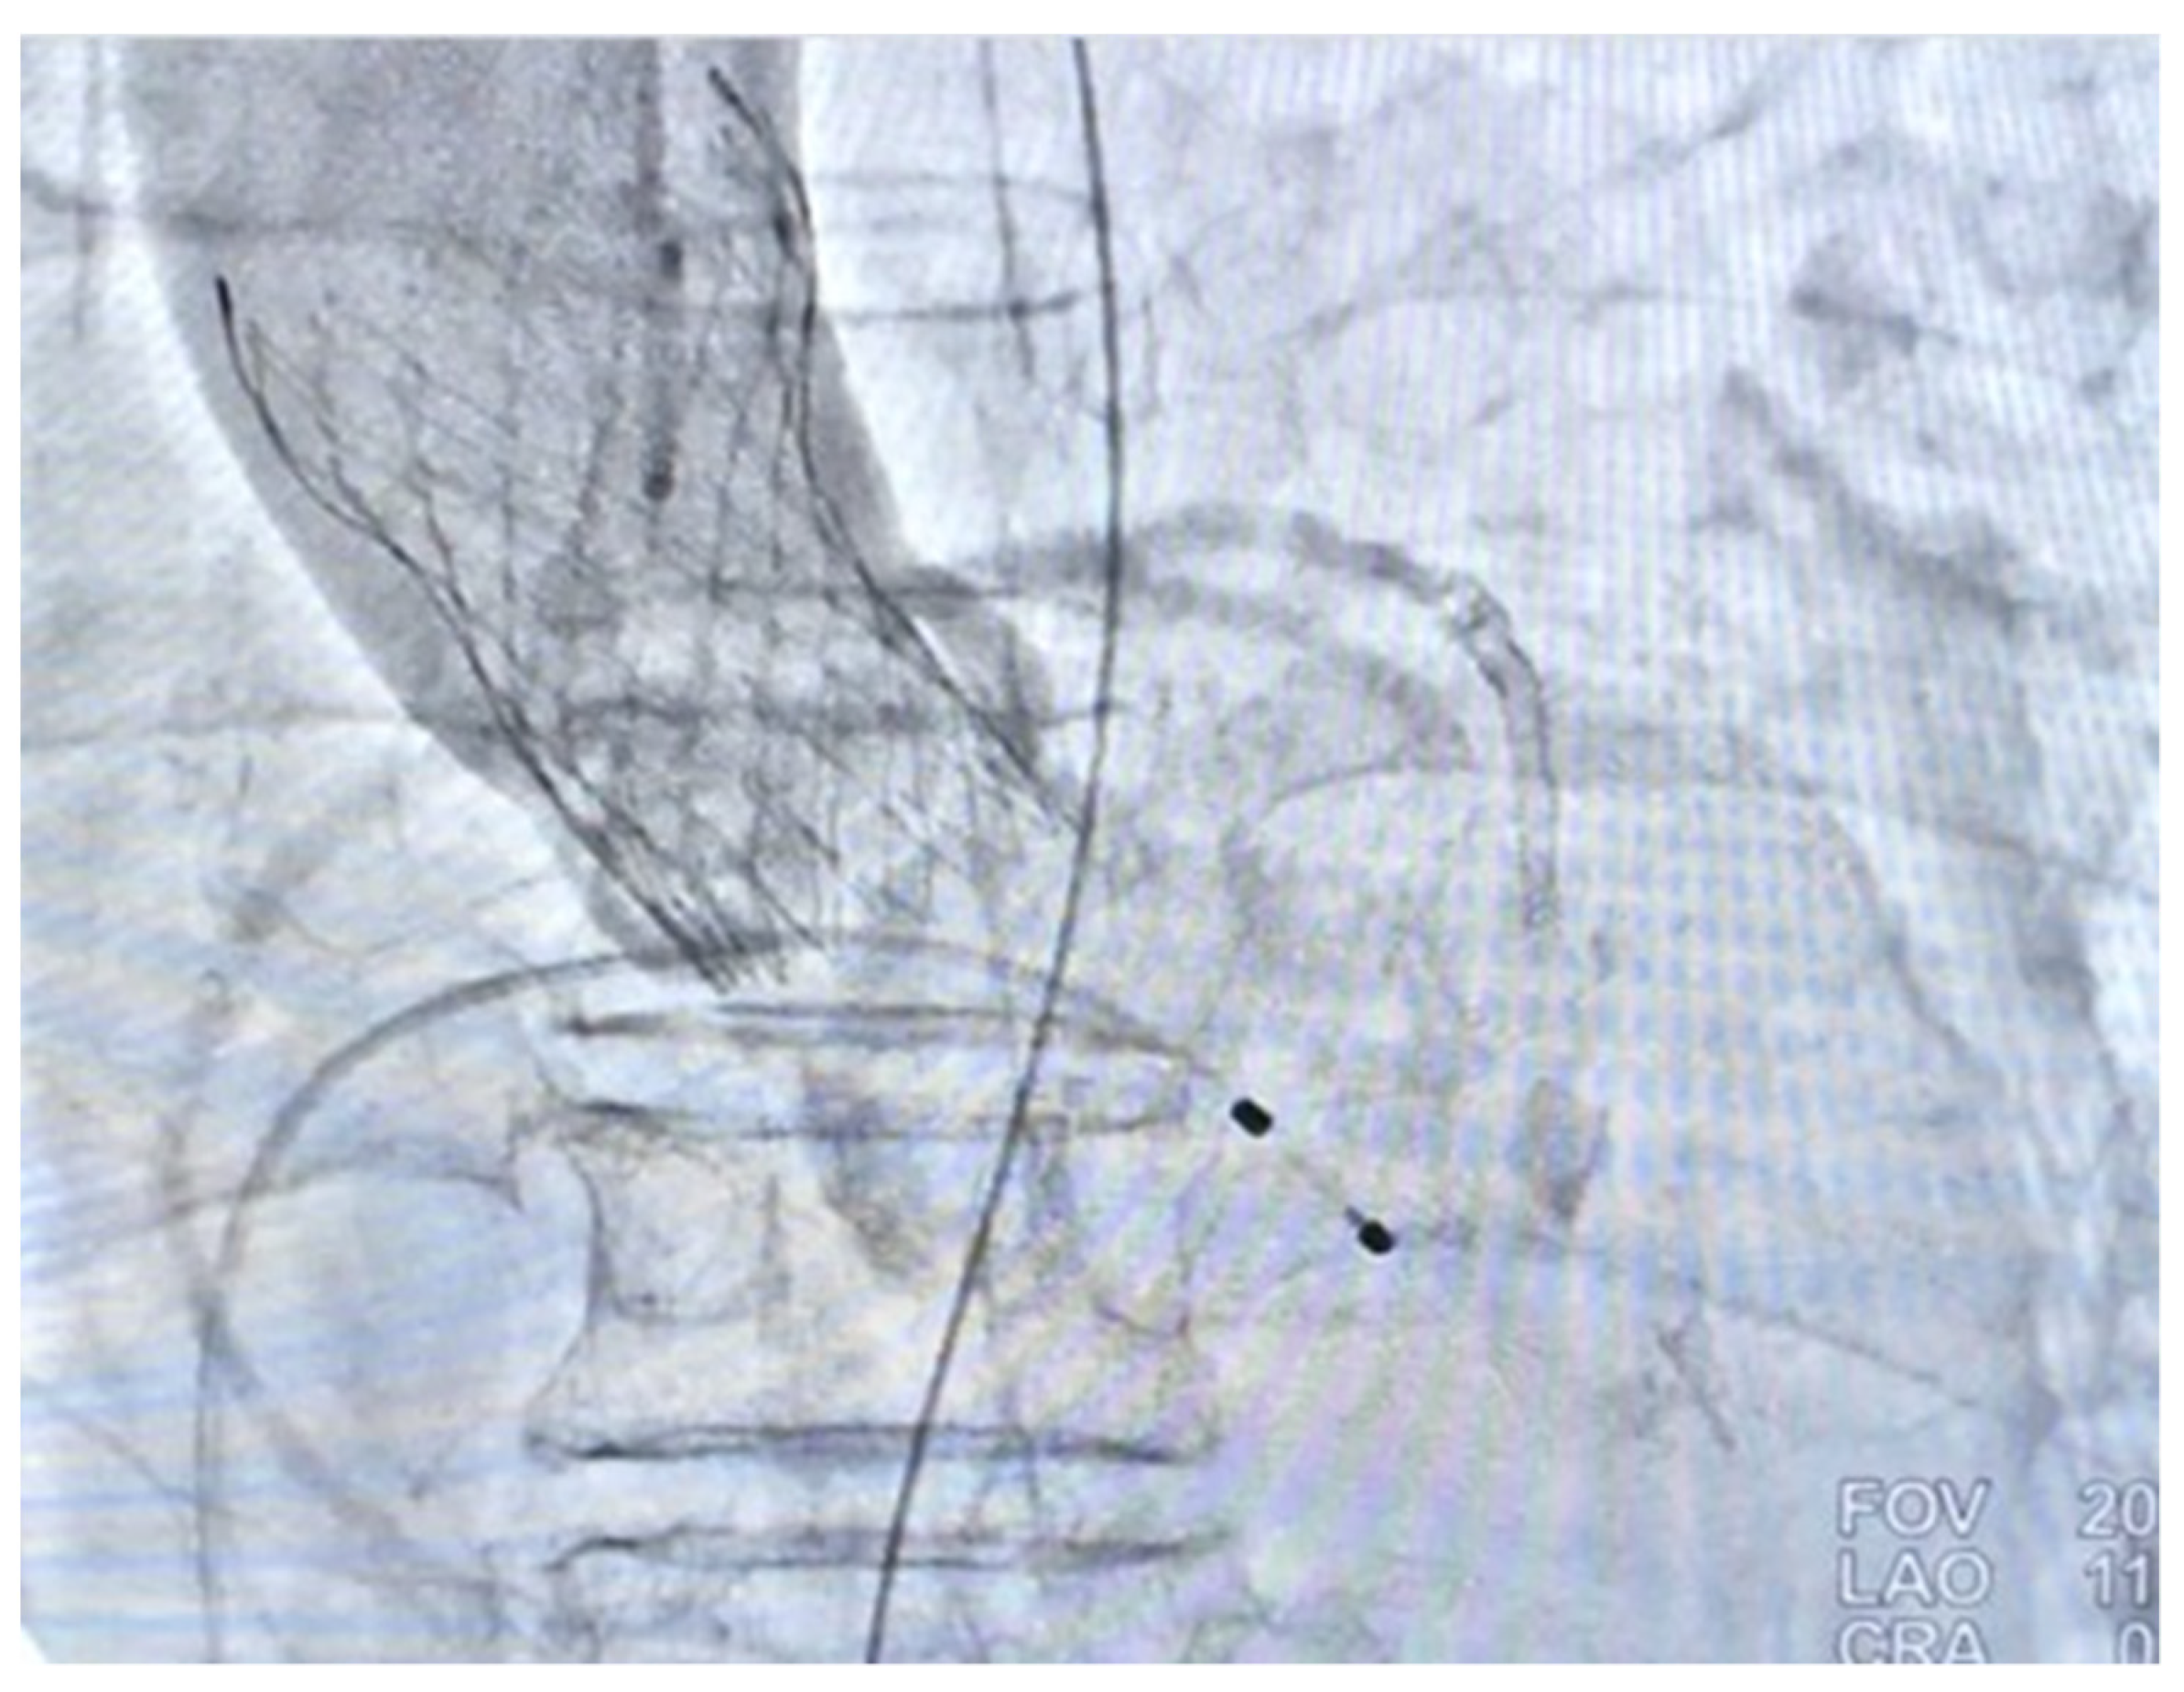

Coronary artery bypass graft (CABG) and surgical aortic valve replacement (SAVR) or percutaneous coronary angioplasty (PCI) and TAVI were suggested to her family. They said they needed a family meeting to discuss it. However, the next day after the coronary angiogram, her dyspnea was more serious and her blood saturation of oxygen was down to 60%. So, she was intubated with mechanical ventilation. Based on her co-morbidities and old age, her logistic Euroscore was 25%, which is high risk (>13%). PCI and TAVI were preferred. PCI was performed next day of intubation, smoothly with two drug-eluting-stents (2.75 mm × 28 mm and 2.5 mm × 28 mm Xience, Abbott, Chicago, IL, USA) in the LAD (Figure 1d). The computed tomography (CT) showed moderate calcification of the aortic valve (Figure 2). Her family requested to wait for an important son coming back from abroad and for her to then receive TAVI. So, she was kept intubated with mild sedation. The patient’s renal function was within the normal limit: blood creatinine was 0.59 mg/dL (normal range 0.50–0.90 mg/dL) before PCI and 0.67 mg/dL after PCI; her hemodynamic condition was stable before and after stent implantation until the night prior to TAVI; four days after PCI, the patient’s vital signs became unstable. Atrial fibrillation (AF) with fluctuated ventricular response and arterial hypotension were noted. Inotropic agent (dopamine 8 μg/kg/min) was given. Upon arrival in the hybrid operation-room, tachycardia atrial fibrillation with about 110 beats per minute bpm was noted. After the induction of general anesthesia, her heart rate dropped to about 60 bpm and she subsequently went into cardiac arrest. Cardiopulmonary resuscitation (CPR) was therefore initiated for about 15 min. A veno-arterial (VA)-ECMO (Capiox, Terumo (Tokyo, Japan; with venous sheath 21 French and arterial sheath 16.5 French) was installed in her left femoral side. Ventricular tachycardia (VT) and ventricular fibrillation (VF) occurred, and 200 joule cardioversion was done twice to restore sinus rhythm. Urgent-TAVI was performed with a 25 mm × 4 cm ZMED2 balloon for pre-dilatation and a 31 mm CoreValve Evolut (Medtronic, Dublin, Ireland) implanted (Figure 3). After the TAVI procedure, she was transferred back to ICU. Despite the sinus rhythm being restored, her LVEF was 22%, which was due to cardiac arrest. We used Levosimendan-therapy and then her LVEF rose to 40%. Pulmonary hemorrhage occurred two days later on ECMO. Her activated partial thromboplastin time (APTT) reached 112.2 s (normal range 24.3–32.7 s). Heparin was held for hours and 10 units of packed red blood cells (RBC) and 4 units and fresh frozen plasma (FFP) were transfused. Then, her APTT was maintained between 50 and 60 s.

Figure 3. Post-TAVI aorta-gram showing mild aortic regurgitation (AR).